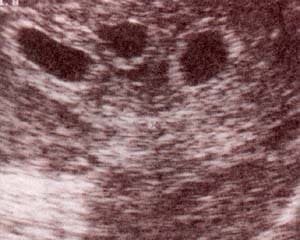

| fig. 53.– (a). gemelar bicorial – biamniótico. signo lambda. se establece precozmente el diagnóstico de corionicidad. en este caso se trata de un embarazo bicorial – biamniótico. | fig. 53.– (b). membrana interamniótica. obsérvese el grosor de la membrana correspondiente a un embarazo gemelar bicorial – biamniótico. |